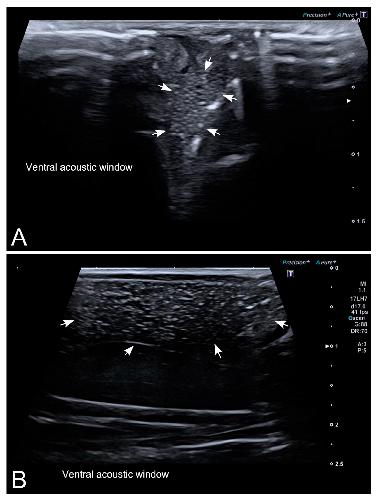

Figure 4. Representative high-resolution ultrasound (HR-US) images of a female Kaloula pulchra obtained in the transverse plane (A) and a female Xenopus laevis (B) obtained in the longitudinal plane using, in both cases, a ventral acoustic window. Follicles appeared as a complex of anechoic or hypoechoic rounded or oval areas separated by hyperechoic lines.

Figure 5. HR-US images of a female Xenopus laevis in the longitudinal plane using ventral (A) and dorsal (B) acoustic windows. Although the complex of follicles is clearly identified in both, the ventral acoustic window was considered more adequate for the examination of female gonads. Nevertheless, the kidney (k) was better identified using the dorsal acoustic window.